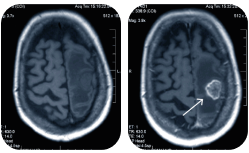

• КТ головы

КТ головы

Компьютерная томография головы в Клинике Эксперт в Красноярске -  это метод медицинского обследования. Его назначают, когда необходимо определить состояние костей и сосудов головного мозга.